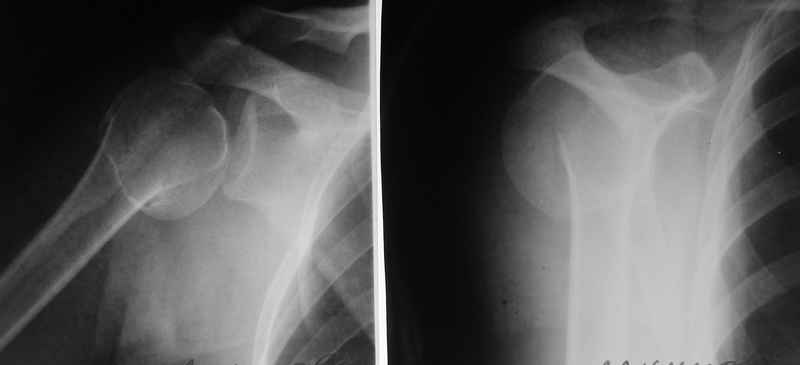

По Neer операцию рекомендовали только тогда, когда угол между диафизом и головкой составляет около 45 градусов, и переломы с меньшим углом смещения считали благоприятным для функционального результата.

Хотя "варусная импакция" в проксимальном отделе плеча срастается хорошо консервативными мерами, но в результате при восстановлении такие больные теряют часть отведения, и тем более у больной варус осложнен еще сгибанием.

Относительно контрольного КТ - впечатление такое, что малость перестарались при репозиции.

Оставлять такой диастаз пожалуй нежелательно. Мы бы вправляли закрыто и фиксирoвали спицами через головку в диафиз - в большинстве случаев получалось неплохо, тем более - перелом вроде двухфрагментарный. ЭОП-контроль на столе - если что-то не так - ORIF.